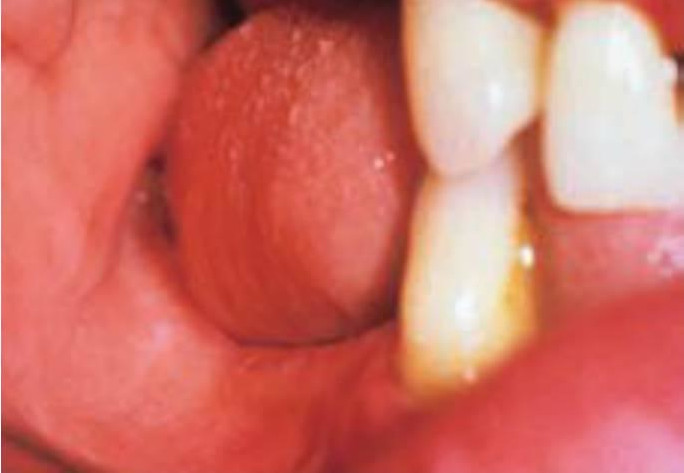

Empuje y tamaño de la lengua

El empuje de la lengua parafuncional es la fuerza no natural de la lengua contra los dientes al tragar60. Se ha registrado al tragar una fuerza de entre, aproximadamente, 41 a 709 g /cm 2 en las zonas anteriores y laterales del paladar. En un movimiento ortodóncico, unos pocos gramos de fuerza son suficientes para desplazar los dientes. Se han identificado seis tipos distintos de empuje lingual; anterior, intermedio, posterior y en todos los casos unilateral o bilateral, y con casi todas las combinaciones posibles (figs. 6-19 y 6-20).

Una pregunta común es qué vino primero la posición aberrante de la lengua o los dientes mal alineados. Independientemente, esta condición puede afectar a la curación de los implantes y dar complicaciones protésicas. Aunque la fuerza del empuje lingual es de menor intensidad en comparación con otras fuerzas parafuncionales, es de naturaleza horizontal y puede aumentar el estrés en el área perimucosa del implante. Esto es más crítico para tratamientos con implantes en una fase, en los que estos se hallan en una posición más elevada en su colocación inicial y la interfase del implante se encuentra en una fase precoz de curación. El empuje lingual también puede contribuir a la apertura de la línea de incisión, lo que puede llegar a comprometer tanto a los tejidos duros como a los blandos.